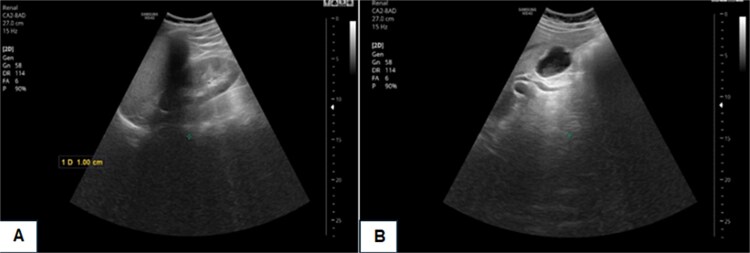

Abstract Image